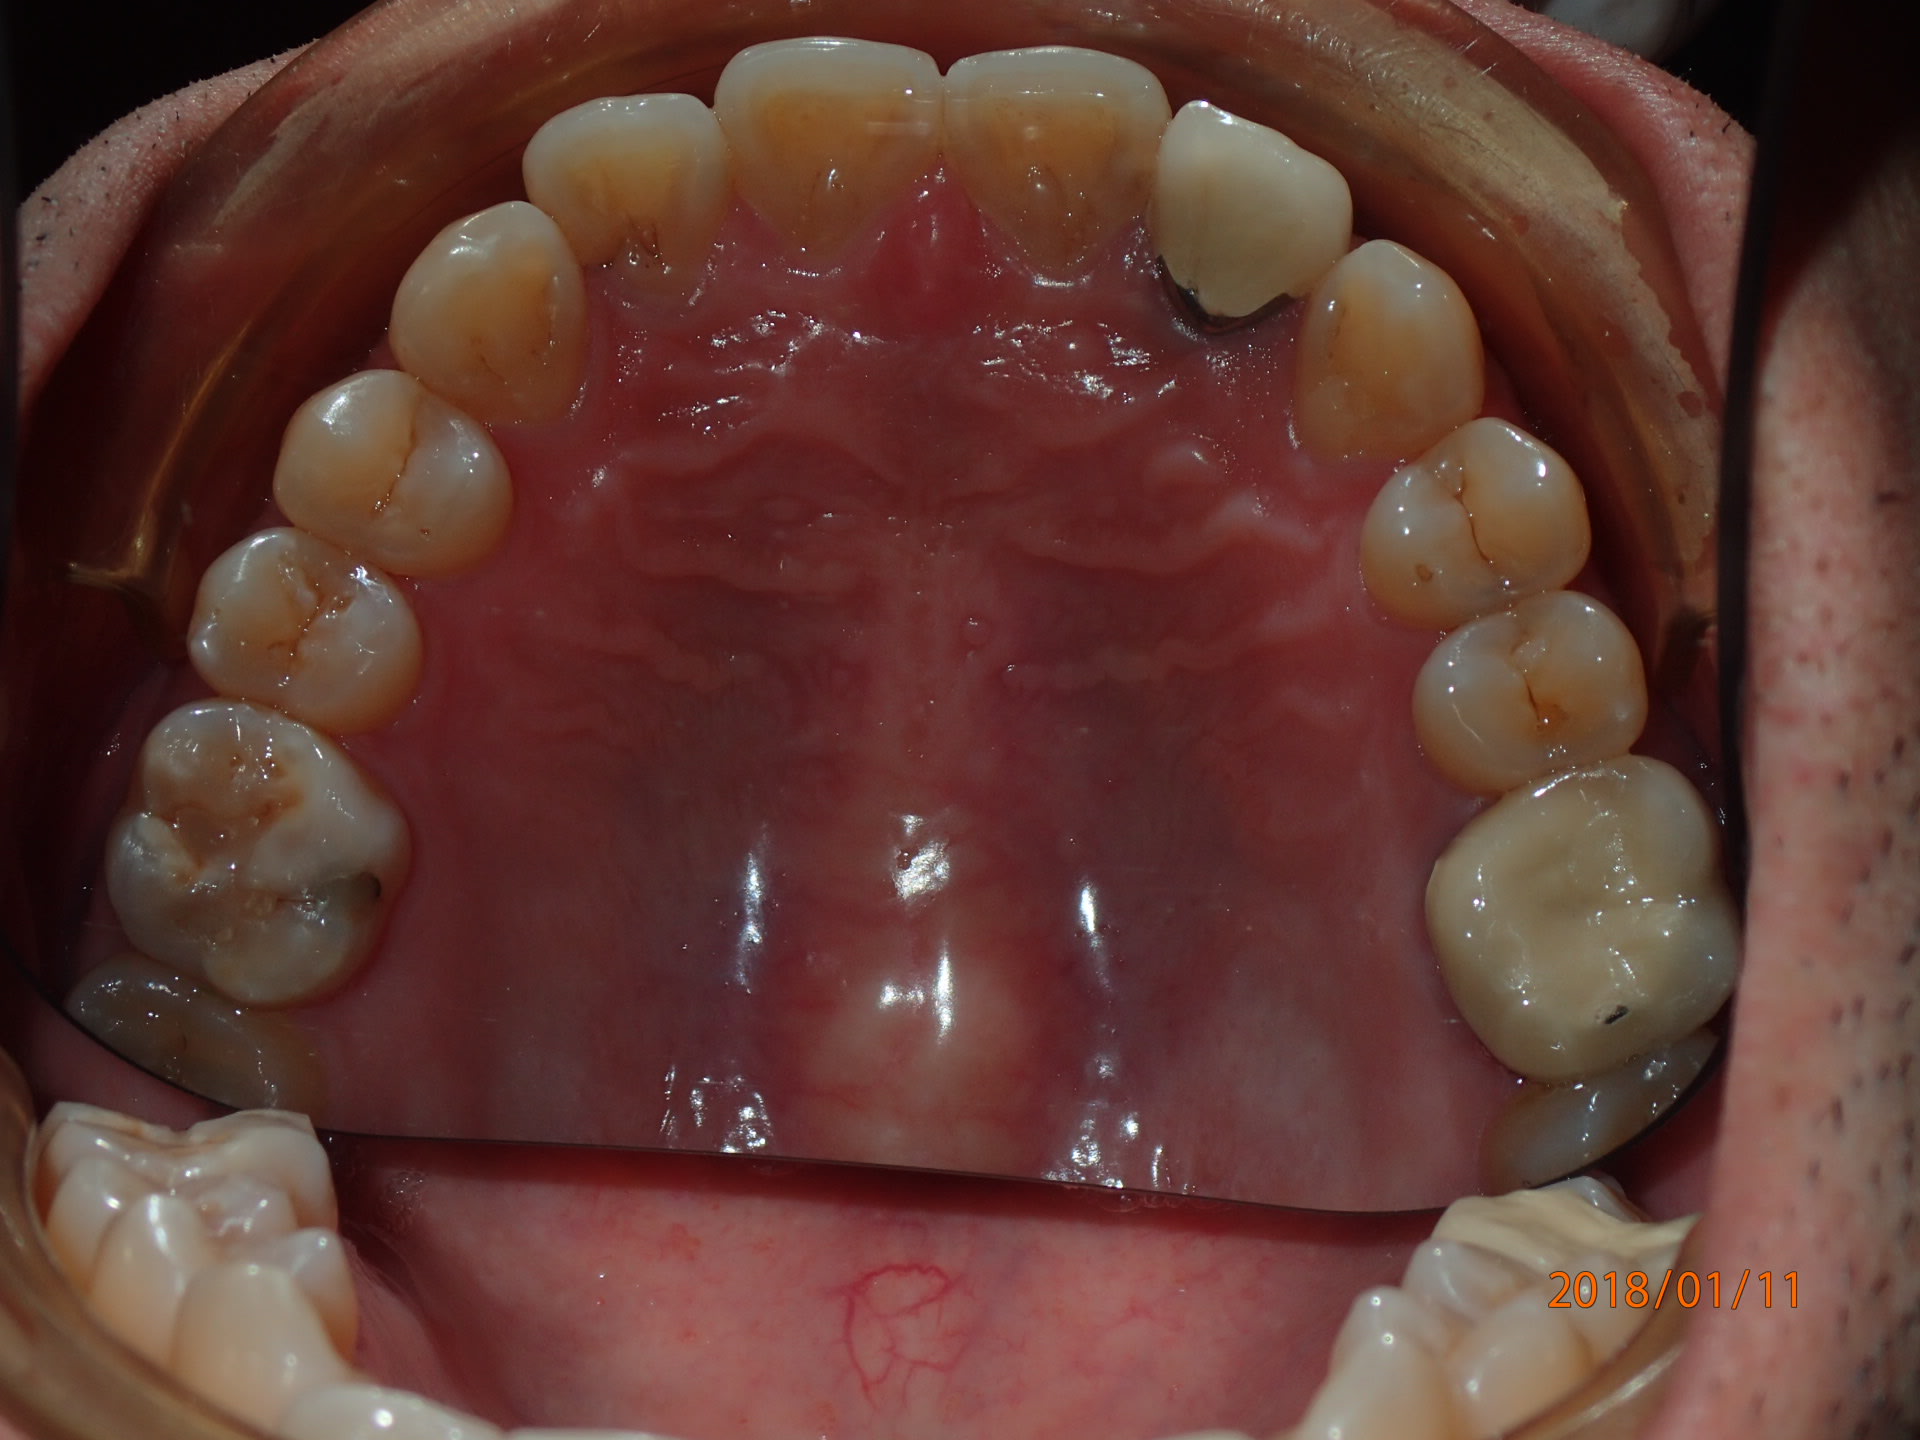

Et mon très probable nouveau cas 2D.

Patient accompagnant un autre patient, en discutant je remarque l'encombrement antérieur mandibulaire et mentionne l'ortho pour lui.

' je suis trop vieux pour des bagues " , je lui explique que le lingual existe, pano, examen.

Il est très tenté par le lingual mais n'est pas sure de vouloir commencer la semaine prochaine, no soucie je prend une simple empreinte alginate et met un rendez vous entre deux patients la semaine d'après. Si il souhaite faire le traitement il doit me confirmer 48 heure avant.

Collage indirect sur les modéle en plâtre en 20 minutes, 5 minutes pour le trays de transfert, 1 minute pour plier le premier fil sur le modéle en plâtre.

Côut du matos endessous de 200$

Aucun autre système lingual n'offre cette réactivité :-)